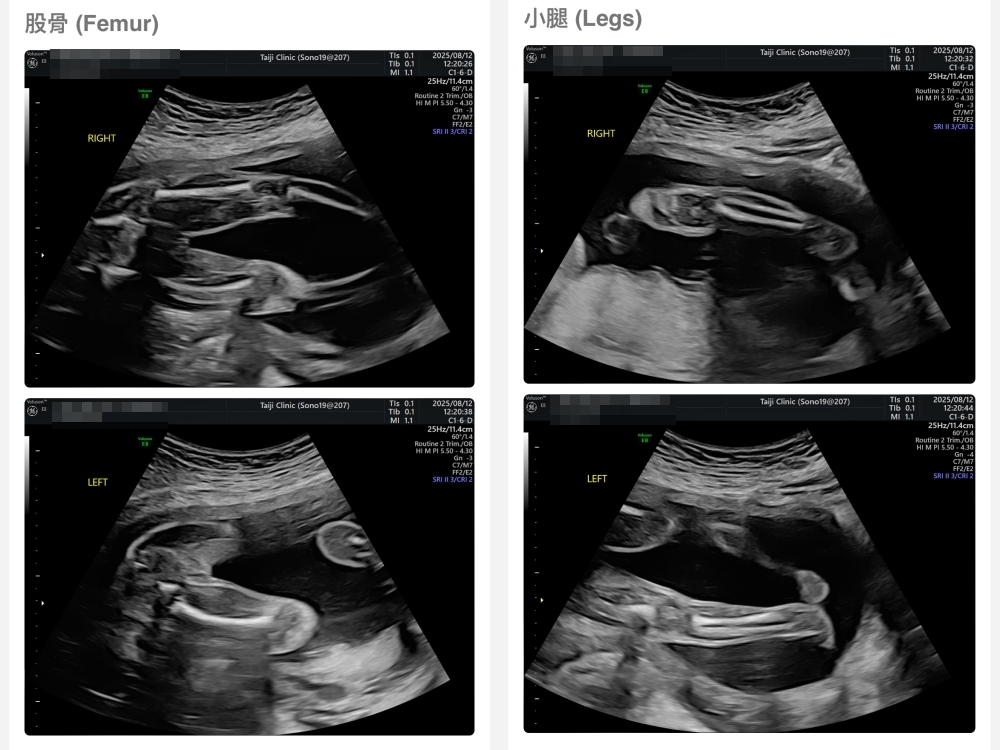

【台兒|高層次超音波|檢查結果】

▲離開診所後會收到MAIL,我們14:05離開,大約是16:45收到mail,裡面會有滿滿的超音波照片,紀錄的很詳細!也會提供紙本的報告,可以給日後產檢的醫師做參考👌